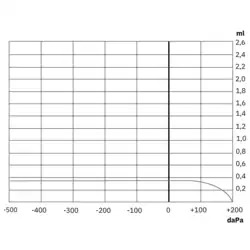

O grau da perda auditiva em indivíduos com otite media secretora varia muito, podendo ser encontrados "limiares normais", menor que 20 dB, até perdas significativas em torno de 50 a 65 dBNA (classificadas como "perdas auditivas de grau moderadamente severo").[15][16]

Na otite média aguda e secretora, ao realizar a audiometria tonal liminar encontram-se perdas auditivas condutivas que podem variar de acordo com a gravidade da otite média secretora. A imitanciometria avalia o grau de resistência da membrana timpânica, apoiando a confirmação da presença de secreção na orelha média ou a existência de pressão negativa na otite média secretora. Os métodos de avaliação utilizados para determinar acuidade auditiva variam dependendo da capacidade da criança em participar dos testes.[22]